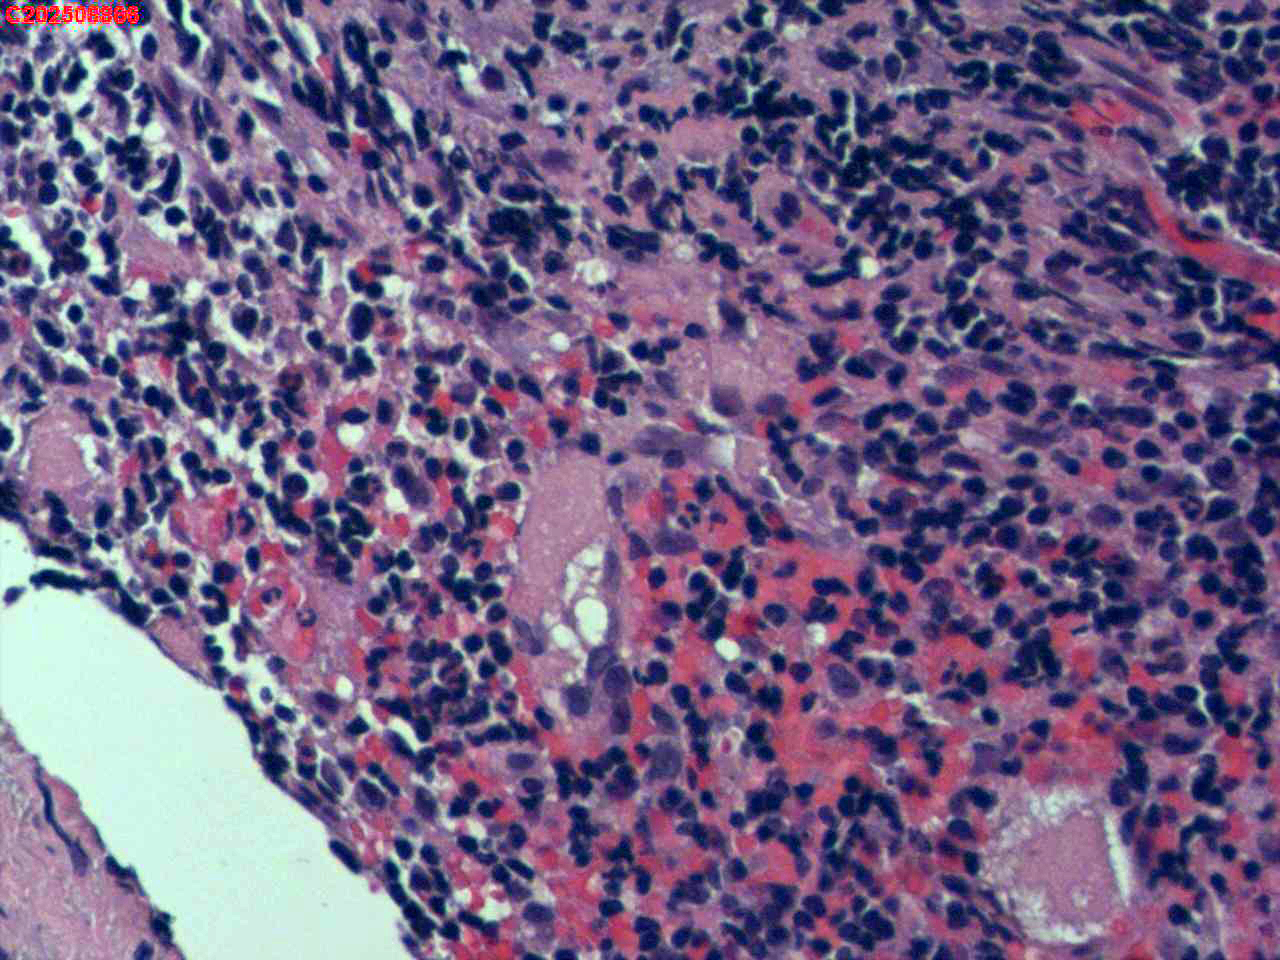

纤支镜咬检

肺TB?Ca?

胸部CT(平扫):考虑双肺感染性病变,结核?支气管炎?请结合临床及其它检查。

标本名称

右肺上叶后段开口咬检组织

大体所见

右肺上叶后段开口处粘膜不规则增生。

肉芽肿性炎的可能性大些!

有坏死,深染变形的细胞需要排一排神经内分泌肿瘤。